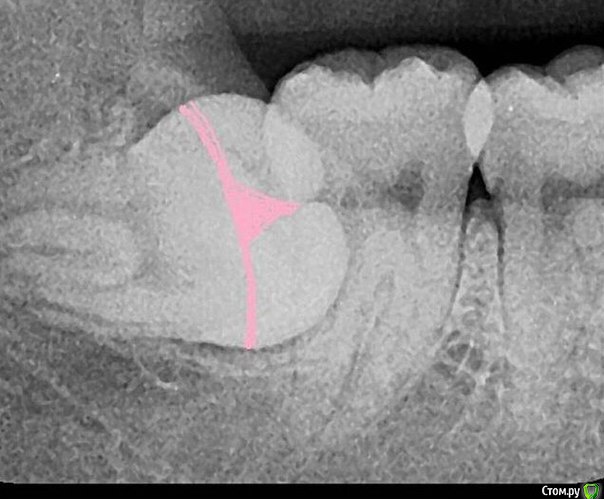

koreandr Опубликовано 24 февраля, 2016 Поделиться Опубликовано 24 февраля, 2016 Не удержался http://s14.radikal.ru/i187/1602/c2/f10b37122b7c.png 8 Ссылка на комментарий

DmitrySH Опубликовано 12 марта, 2016 Поделиться Опубликовано 12 марта, 2016 Можно было тонкие файлы (без ручки) в апексы засунуть 2 Ссылка на комментарий